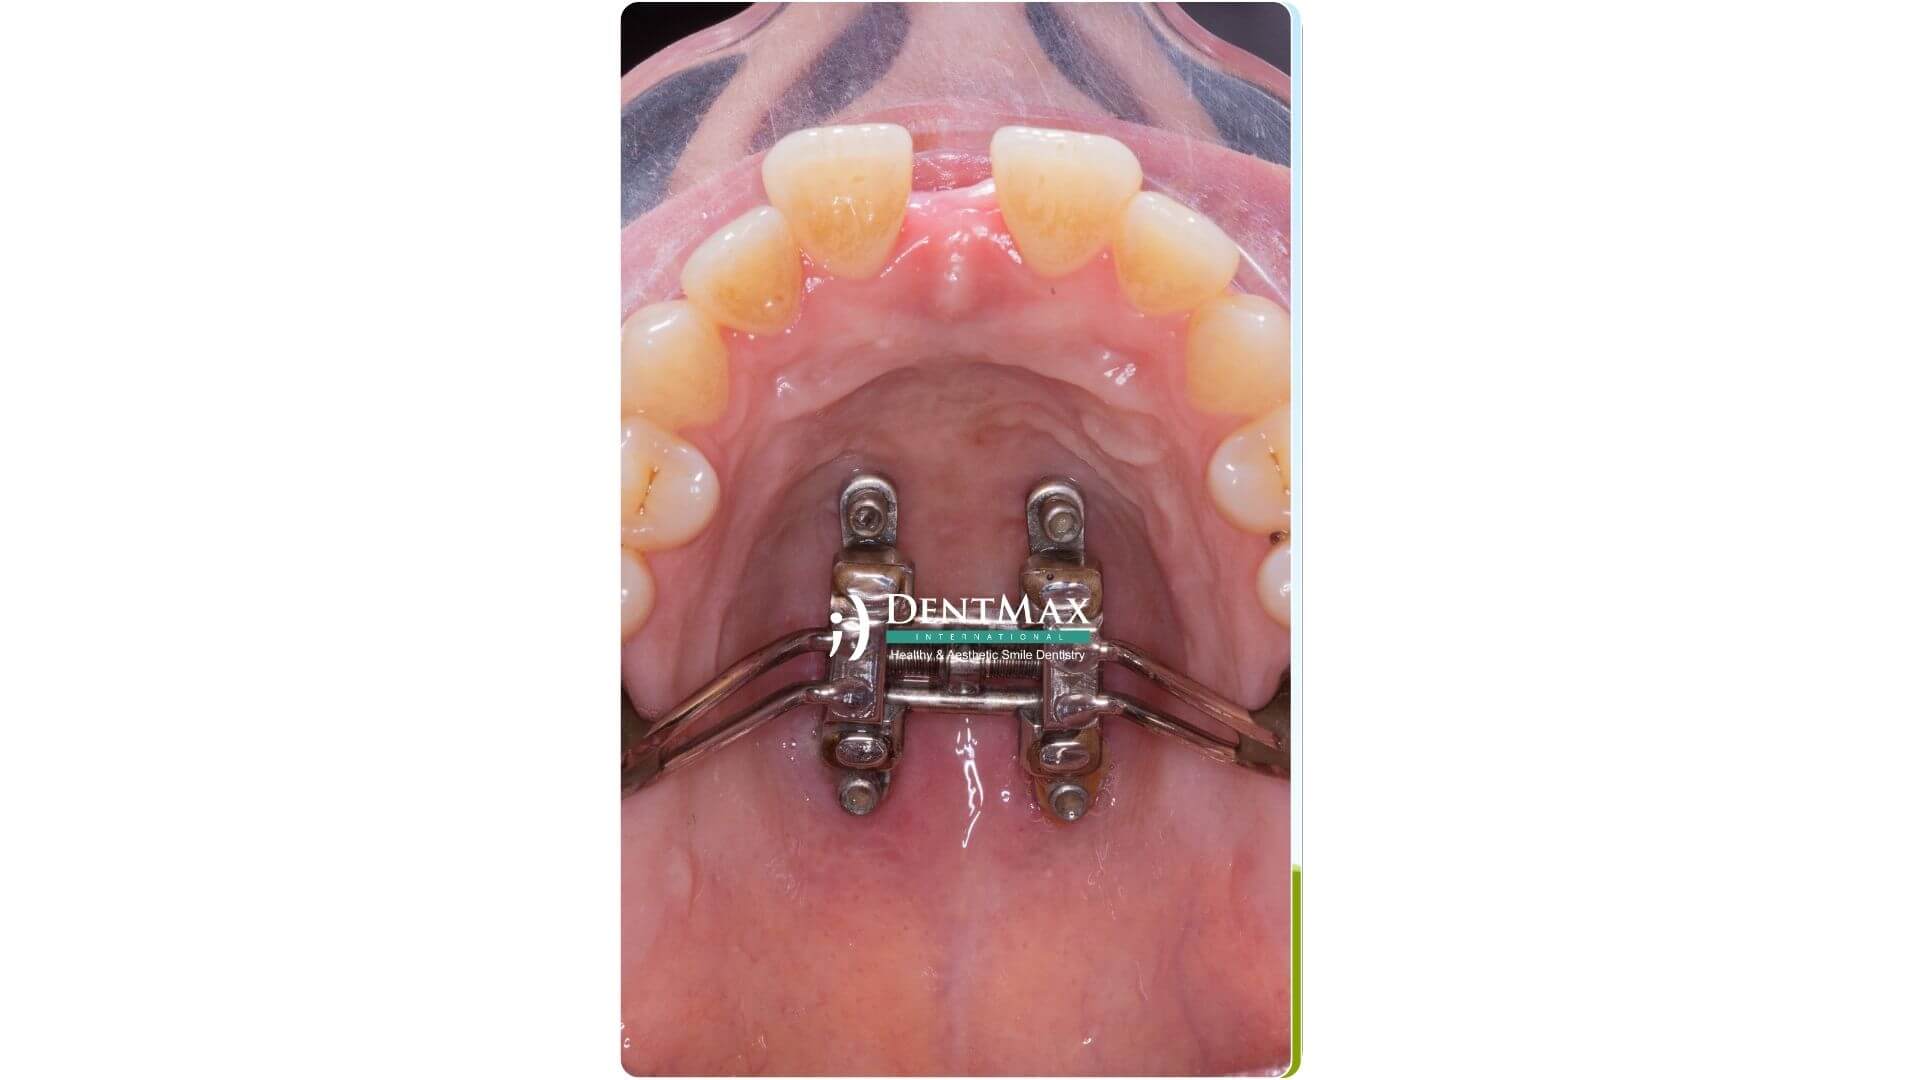

RME (Expansion Maxillaire Rapide) | Appareils utilisés pour élargir la mâchoire supérieure. RME fournit une expansion rapide et peut être utilisé en toute sécurité chez les individus jusqu'à 16 ans. C'est 100 % efficace. |

RME (Expansion Maxillaire Rapide) | Une méthode pour élargir rapidement la mâchoire supérieure. Fournit une expansion naturelle et très efficace. |

Traitement chez les adultes (16 ans et plus)

Chez les adultes, le traitement de la mâchoire supérieure étroite nécessite généralement une combinaison de traitements chirurgicaux et orthodontiques. Les méthodes de traitement appliquées dans cet âge...